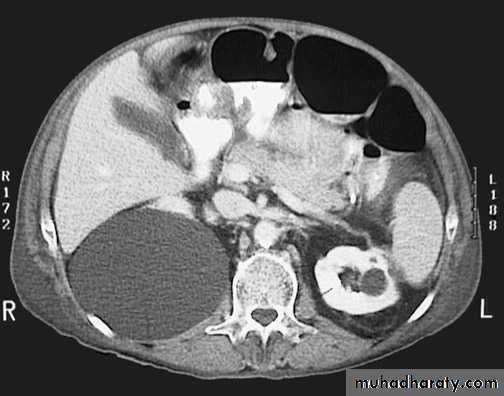

Horseshoe Kidney

found in 1:1000 necropsies an is commoner in men.

probably the most common of all renal fusion anomalies

The anomaly consists of two distinct renal masses lying

vertically on either side of the midline and connected at

their respective lower poles by a parenchymatous or fibrous

isthmus that crosses the midplane of the body.

Fusion of the renal masses early in embryonic life, so its ascent

will be impeded by inferior mesenteric artery.

The kidneys are low located, mal rotated and pelves lie anteriorly

Symptom When present, they are related to complications like hydronephrosis, infection, or calculus formation

Diagnosis ultrasound, IVU, CT scan